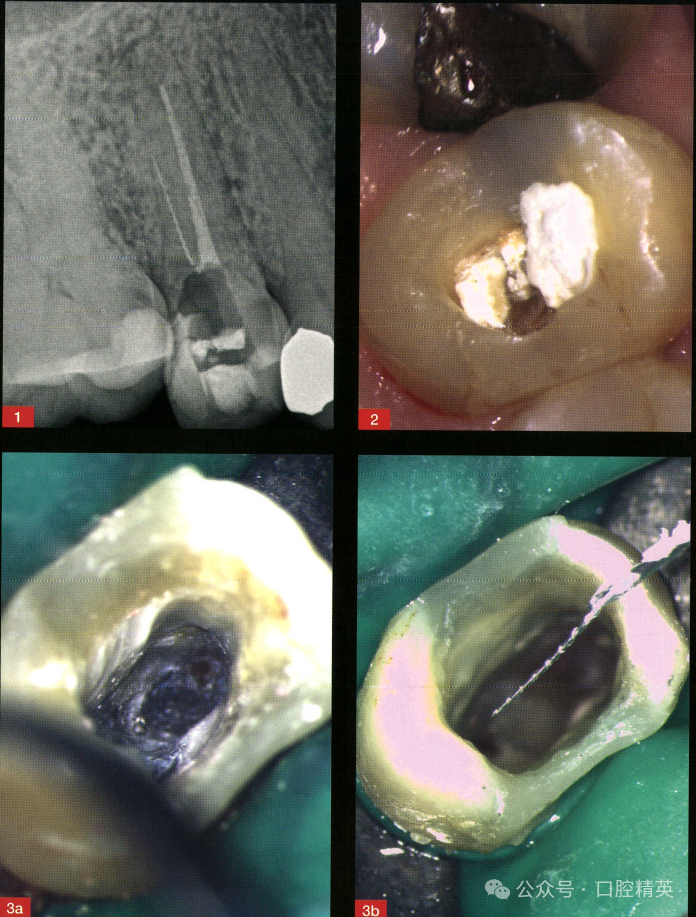

转诊患者,女性,58岁。影像学检查发现,右上第二前磨牙颊侧根管中上段可见分离器械(图1)。治疗计划是取出分离器械并完成根管再治疗(图2~图4)。

图1术前X线片显示颊侧根管内存在分离器械,腭侧根管充填不全。

图2超声器械去除不良修复体。

图3a,b修整开髓洞口,暴露分离器械上端(a),插入恰当的针头和胶水以固定并取出器械。

27号冲洗针头(BD MicrolanceTM 3针头27G×3/4"-0.4mm×19mm)和氰基丙烯酸酯胶水配合可取出分离器械,然后对患牙进行根管预备、消毒和充填,最后复合树脂直接修复。在本病例中,与其他分离器械取出技术相比,联合使用冲洗针头和氰基丙烯酸酯胶水是一种经济有效的处理方法。